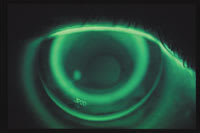

Figure 2: Photo of RG lens with correct sag depth |

Figures 1 and 2 show an ideal fit. Figure1 shows the lens just returning to the cornea at the outer edge of the secondary zone, and the alignment/landing zone of the lens is parallel to the cornea. In Figure 2, note the wide area of central touch, followed by pooling in the secondary zone and alignment in the periphery. When this type of fit is achieved, the sagittal height of the lens is close to the sagittal height of the cornea. This is the goal for effective treatment.